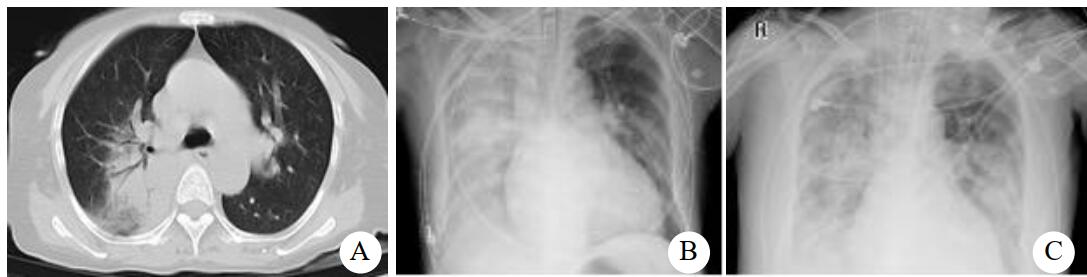

入院查体:体温39 ℃,脉搏87次/min,呼吸30次/min,血压111/75 mmHg(1 mmHg=0.133 kPa);神清,无皮疹,浅表淋巴结无肿大,双肺闻及少许干湿啰音,心律齐,未闻及杂音,腹软,肝脾肋下未触及;胸部CT示两肺感染,见图 1;甲、乙型流感病毒抗原检测阴性。入院诊断:重症社区获得性肺炎。予无创机械通气,莫西沙星抗感染,帕拉米韦抗病毒治疗,效果欠佳,遂转入ICU。入ICU血气:FiO2 70%,pH 7.44,PCO2 30.5 mmHg,PO2 88.2 mmHg,Lac 0.9 mmol/L,PO2/FiO2 126.0,考虑合并急性呼吸窘迫综合征,予气管插管机械通气,右美托美定+丙泊酚镇静、哌拉西林他唑巴坦、奥司他韦、甲泼尼松龙等治疗。复查胸部CT示:两下肺实变。行俯卧位通气,行肺泡灌洗液mNGS检测:鹦鹉热衣原体(序列数773),未检测到病毒及其他细菌,改用多西环素+莫西沙星抗感染。治疗效果好,1周后复查肺CT示病灶吸收明显,见图 2;第10天脱机拔管,转出ICU。

| 两肺斑片状密度增高影,边界模糊,两下肺大片实变影 图 1 病例1入院时胸部CT结果 |